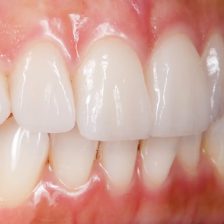

審美治療